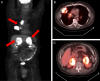

Current treatment paradigms for oligometastatic non-small cell lung cancer (NSCLC) utilize systemic chemotherapy alone or in combination with immune checkpoint inhibitors (ICIs). The addition of ICIs in NSCLC has led to significant improvements in survival; however, recurrence remains common. New methods are needed to enhance anti-tumor immune responses and improve patient outcomes. Here, we present the first case of utilization of the Ethos OART platform to deliver multi-site pulsed hypofractionated radiotherapy in a patient with oligometastatic disease on the single arm prospective clinical trial SiCARIO (Split-Course Adaptive Radioimmunotherapy in Oligometastatic NSCLC, NCT05501665). A 67-year-old man with stage IV NSCLC with metastases to bilateral adrenal glands, retroperitoneum, and mesentery was prescribed treatment of 40 Gy in 5 fractions on SiCARIO in combination with SOC chemoimmunotherapy. A multi-target single isocenter approach was utilized to treat nine distinct targets in five total isocenters. Treatment plans were generated using an isotopic approach prioritizing organ at risk (OAR) constraints with the goal of minimum coverage of at least 30 Gy in 5 fractions. CBCT was acquired with each fraction to generate new targets and OAR contours based on anatomic changes with the patient on the treatment table. A comparison of an adapted plan to a base plan was performed online with a selection of superior plans based on target coverage and OAR constraints. The adapted plan was deemed superior for all but 1 fraction of a single isocenter for this patient. The discussion will focus primarily on the bilateral adrenal isocenter, where bulk tumor shrinkage of greater than 80% was observed in this patient with corresponding significant dosimetric benefits. This case demonstrates a potential clinical benefit of OART in multi-metastasis RT. Further data is needed to confirm the safety and efficacy of this approach. Enrollment is ongoing.